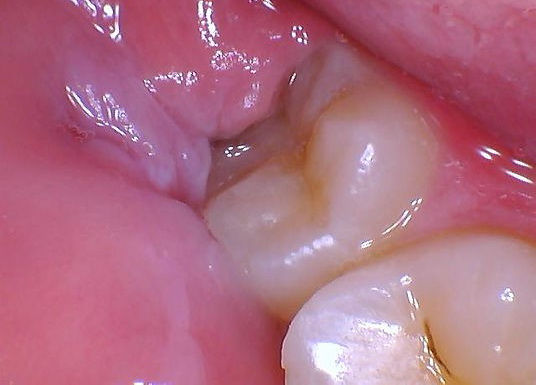

Impacted wisdom teeth

Impacted wisdom teeth are a condition caused by a serious deviation in the growth angle of the wisdom teeth. When the wisdom teeth and gums are close to 90 degrees vertical, it is called "impacted wisdom teeth." Impacted wisdom teeth are more likely to become impacted, meaning that the wisdom teeth lack space to grow above the gums because they are blocked by other teeth. Impacted wisdom teeth can cause inflammation, toothache, and periodontal disease, so extraction should be considered depending on the situation.

Wisdom tooth decay

Wisdom teeth are prone to impaction. Impacted wisdom teeth are very difficult to clean, both on the teeth themselves and in the gaps between other teeth. Food debris and dental plaque can easily accumulate, making wisdom teeth more difficult to clean. Prone to tooth decay, if this is the case, it is recommended to remove wisdom teeth to eradicate the problem.